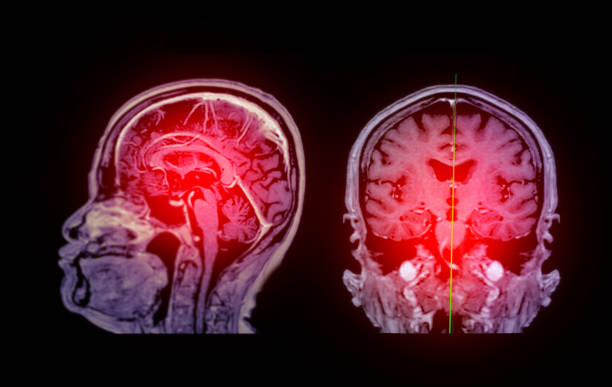

腦缺血缺氧引起的缺血性腦卒中是一種致殘率較高的腦血管疾病。缺血性中風是全世界殘疾和死亡的主要原因。據報道,缺血性腦卒中30天內的死亡率為5%~15%,致殘率可能超過50%。超過40%的幸存者再次經歷缺血性中風,死亡率和致殘率更高。

目前,重組組織型纖溶酶原激活劑標準靜脈溶栓療法是臨床上唯一批準的治療急性腦梗死的藥物療法。然而,這種治療方法也有局限性,主要與其在癥狀出現后4.5小時的短暫窗口期內應用有關。血管內介入治療的應用也越來越多,但仍僅適用于大血管閉塞的患者。不適合溶栓治療或血栓切除術的患者的致殘率甚至更高??祻椭委熾m然有助于神經功能的恢復,但療效仍然有限。

迄今為止,大量臨床前研究表明,干細胞可以通過多種機制改善腦缺血損傷后神經功能的恢復。這包括抑制炎癥、促進軸突再生和神經保護作用。盡管如此,干細胞治療缺血性中風的臨床試驗還很少。

近期,福建醫科大學第二附屬醫院神經外科《Medicine (Baltimore)》期刊雜志發表了一篇《干細胞治療缺血性中風的療效和安全性:薈萃分析》的文獻綜述,該綜述表明干細胞療法可降低缺血性中風患者的死亡率并改善神經學預后。

概述結果:對納入592名缺血性中風患者的13項研究進行了回顧。mRS,NIHSS和BI顯示了干細胞治療缺血性中風的有效性。死亡率顯示干細胞治療改善了預后并降低了死亡率。

干細胞療法可降低缺血性中風患者的死亡率并改善神經學預后。然而,由于所使用的干細胞類型不同,且已報道的研究數據有限,因此必須仔細評估干細胞臨床應用在缺血性腦卒中患者中的安全性。未來有必要利用受控細胞來源的大樣本進行隨機對照試驗來驗證這一發現。